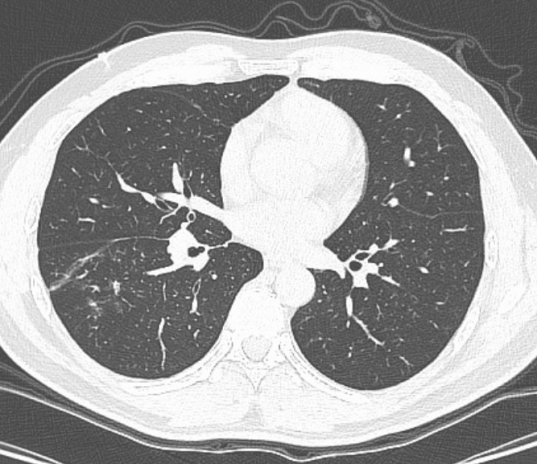

术后抗感染1周后复查的胸部CT

异物取出后,困扰陈先生多日的咳嗽、高热迅速缓解。科室团队全程跟进,制定规范个体化的后续治疗方案,经过1周抗感染治疗,复查CT显示肺部炎症明显吸收;住院第10天,陈先生便顺利康复出院,重归正常生活。“小小一段酸豆角,差点闯下大祸,多亏呼吸科团队及时出手、妙手回春!”出院时,陈先生满是感激与后怕。